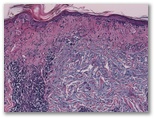

a) La dermatomiositis

b) el lupus eritematoso (dermatitis lupus)

c) Drogas - tipo de interfaz

d) El liquen plano, el tipo de parte atrófica

e) enfermedad de injerto contra huésped